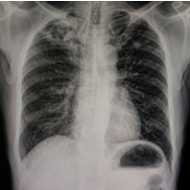

Longfibrose is een chronische aandoening waarbij er bindweefsel, of littekenweefsel, gevormd wordt in de longen. De aandoening is agressief. Het is belangrijk om de ziekte in een vroeg stadium vast te stellen en snel met een behandeling te starten.

Longfibrose is een chronische aandoening waarbij er bindweefsel, of littekenweefsel, gevormd wordt in de longen. Het gevolg is dat de wand van de longen dikker wordt en het lichaam onvoldoende zuurstof kan opnemen.